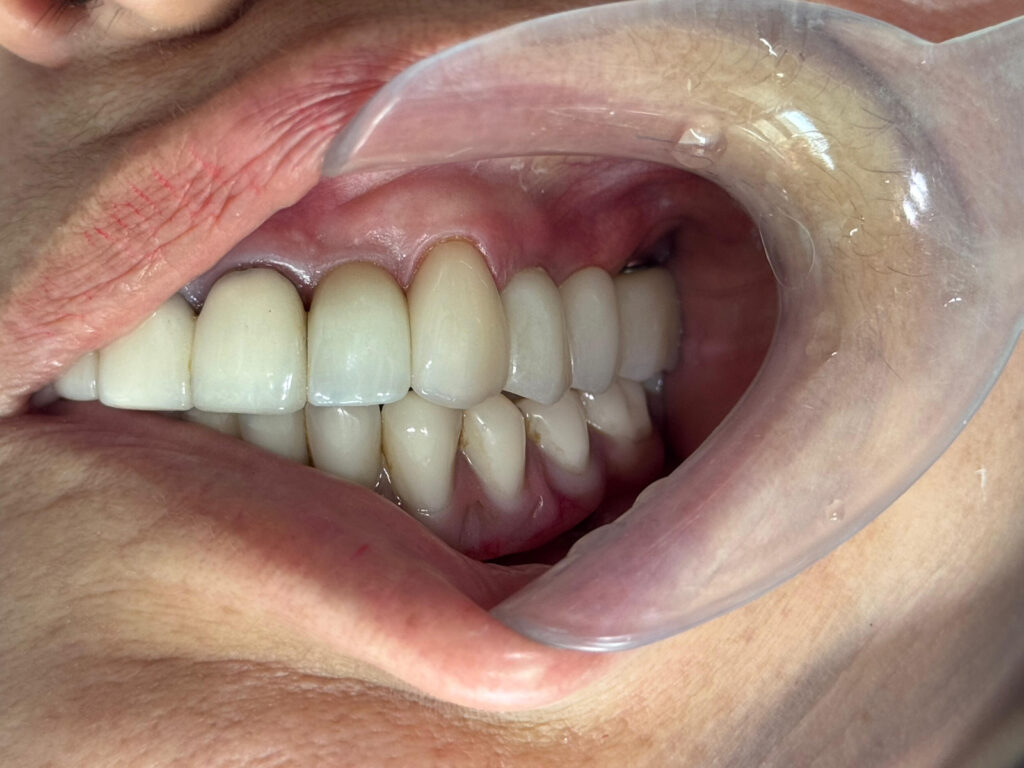

Coronas sobre implantes en Quito: la pieza final para recuperar tu sonrisa

Cuando se pierde un diente y se coloca un implante dental, el tratamiento no termina…